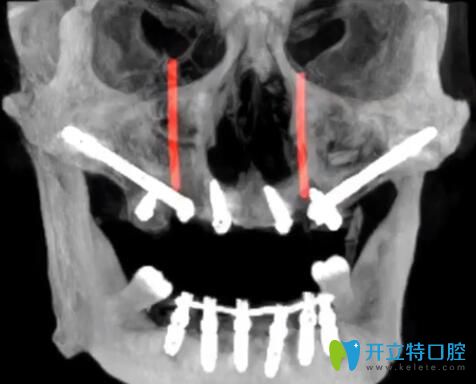

1、TPP穿翼板種植技術(shù)——牙槽骨條件差也能1天種好牙

大家知道種牙的必要條件就是有足量的牙槽骨,針對牙槽骨萎縮的人群,傳統(tǒng)的種植方法是骨增量,過程相對復(fù)雜,而且需要1年的恢復(fù)期。而黎強(qiáng)醫(yī)生的TPP穿翼板種植技術(shù),避開血管,把種植體種在牙齒與咽喉交界附近的十分堅(jiān)硬的“翼狀板骨”上,將傳統(tǒng)種植1年才能解決的問題,在1天內(nèi)種好牙,且遠(yuǎn)期效果好。

TPP穿翼板種植技術(shù)